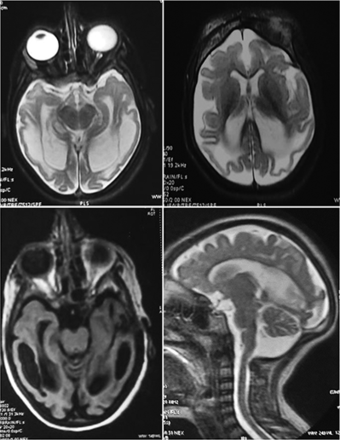

我们描述一个病人头小畸型与早发性癫痫(MCSZ)来自印度次大陆窝藏2小说的突变PNKP,包括一个叉形头的致病性突变相关的领域。此外,我们确认MCSZ与hyperactivation单根打破传感器蛋白质聚(ADP-ribose)聚合酶1 (PARP1)流产拓扑异构酶诱导后我活动,DNA链断裂的来源之前与神经系统疾病有关。

这些数据的频谱扩展PNKP突变与MCSZ和显示PARP1在未修理的hyperactivation topoisomerase-induced DNA断裂是这种疾病的分子特性。